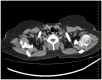

Coronavirus disease-19 caused by severe acute respiratory syndrome Corona virus-2 is characterised by wide heterogeneity in clinical presentation. The typical radiographic findings in COVID-19 include bilateral ground-glass opacities and/or consolidations predominantly affecting the lower lobes and posterior segments of lungs. Other rare abnormal radiographic findings include pneumothorax, pneumomediastinum and pneumopericardium. There has been an increased incidence of pneumomediastinum, a rare but potentially life-threatening complication during this pandemic. It may be spontaneous or secondary. Pneumomediastinum may be due to barotrauma, cytokine storm induced diffuse alveolar injury or direct viral infection of type I and type II pneumocytes. The presence of pneumomediastinum in COVID-19 patients may indicate extensive alveolar membrane destruction and those patients need close monitoring. There are no consensus guidelines in managing COVID-19 patients with pneumomediastinum. Higher mortality rates (70.58%) are reported in intubated COVID-19 patients with pneumomediastinum. The development of pneumomediastinum in COVID-19 should be considered as a poor prognostic factor.